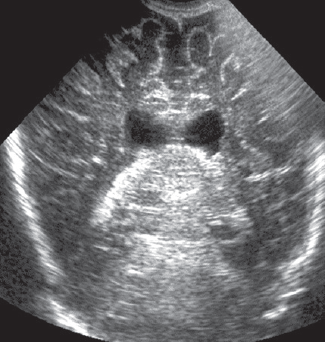

Рис. 2. Магнитно-резонансная томограмма головного мозга пациента, сагиттальный срез. Визуализируется гиперинтенсивный сигнал в области базальных ядер (тонкая стрелка), прецентральной извилины (толстая стрелка) / Fig. 2. Patients brain, magnetic resonance imaging, sagittal. Abnormal T1 hyperintensity is presented at the level of thalamic (thin arrow), motor cortex (thick arrow)

На 27-й день жизни выполнена МРТ головного мозга, диагностирована гипоксически-ишемическая энцефалопатия с двухсторонним поражением базальных ядер, ножек мозга, прецентральной извилины и гиппокампов. Кроме того, выявлена смешанная гидроцефалия по заместительному типу (рис. 1, 2). Визуализируется симметричное усиление МР-сигнала в области базальных ганглиев (рис. 1, а), гиппокампов (рис. 1, b), также определяется значительное расширение субарахноидальных пространств, преимущественно над лобными, височными долями больших полушарий с расширением сильвиевой щели, расширение борозд и истончение коры больших полушарий (наружная гидроцефалия по заместительному типу), расширение передних отделов боковых желудочков.